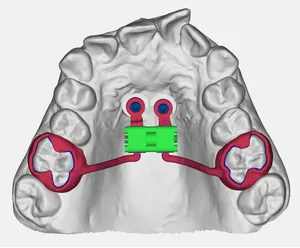

Distalizzatore Tooth Borne

Dispositivo per la distalizzazione molare con ancoraggio dentale. Progettato digitalmente per massimizzare l'efficacia del movimento e minimizzare gli effetti collaterali indesiderati.